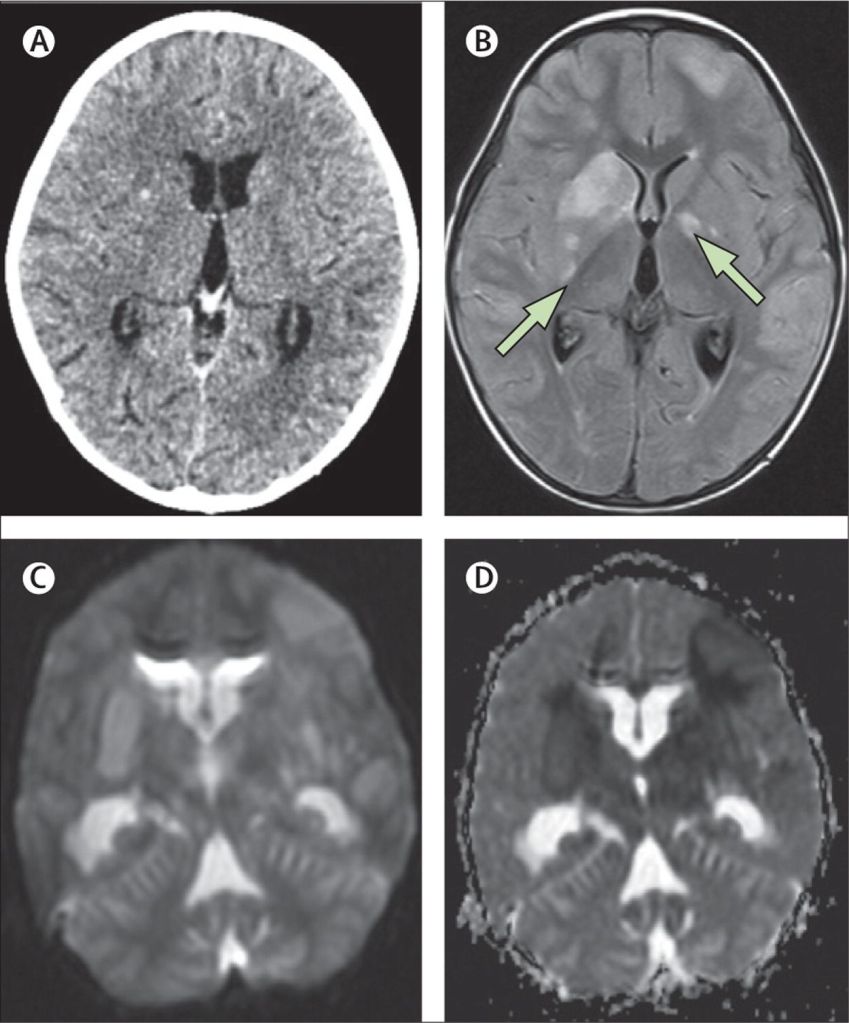

b) TB Meningitis: Evidence suggests that EPTB can seed the central nervous system, leading to life-threatening inflammation of the brain membranes.